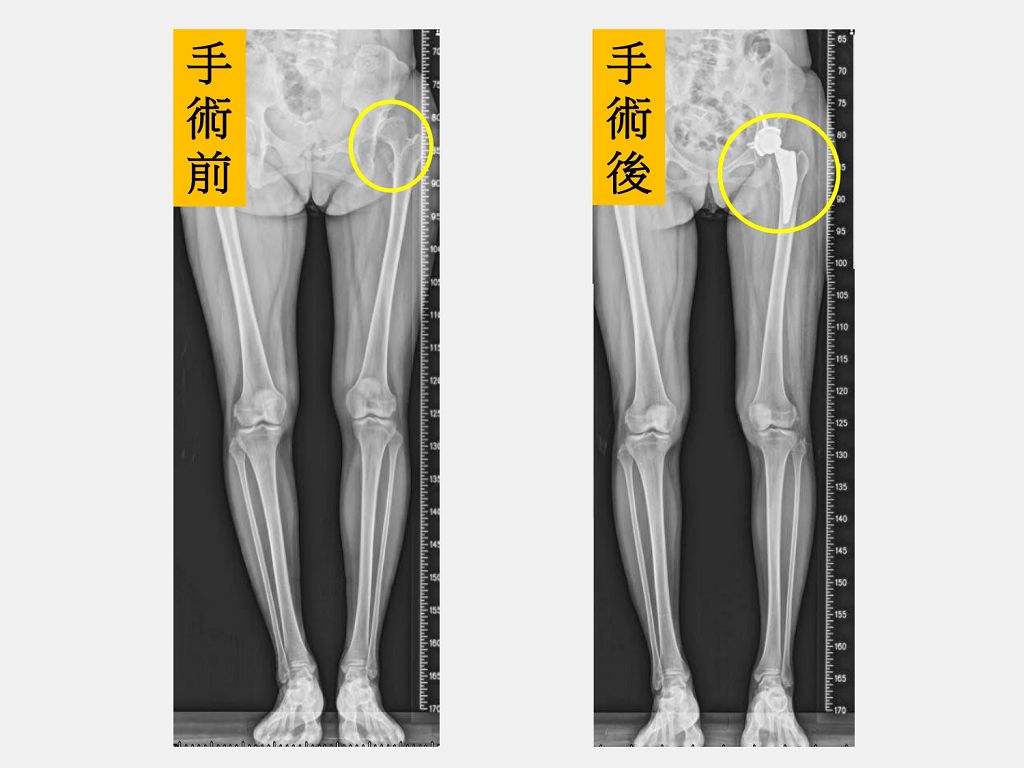

34歲的陳小姐因為左邊髖關節發育不良在幼兒園和小學時分別接受過2次髖關節截骨矯正手術。然而,在走路時卻始終還會有卡卡的感覺,運動後也常常痛到像企鵝一樣一跛一跛的。隨著小孩上小學後活動越來越多,參加活動常常讓她痛到力不從心,羨慕其他的媽媽們可以全心全意陪伴小孩成長,不想缺席卻又不得不吃止痛藥硬撐著,糾結的心情讓她鬱悶到幾乎快得了憂鬱症。陳小姐接受仁愛長庚合作聯盟醫院(大里仁愛醫院)骨科部黃贊文部長建議選擇「微創正前開髖關節置換手術」治療,經過2個月的肌肉訓練,已經幾乎恢復正常生活,計劃在小孩小學畢業後一起去日本旅行,終於重回人生軌道。

黃贊文部長表示,陳小姐因為長年疼痛和不能好好參加小孩的社團發表、學校活動讓她看起來非常憂鬱,也轉介給身心科醫師一同協助。陳小姐左側髖關節和大腿因為曾經手術2次有著長達30公分疤痕,肌肉也有明顯的萎縮,因此建議進行「微創正前開髖關節置換手術」。陳小姐在手術當天下午麻醉藥效一退,就開始練習騎腳踏車運動,陳小姐說,原本以為會很痛,但完全沒有痛的感覺,2隻腳也一樣長了,腳踩在地上的感覺非常不真實,就像是睡了一覺做了一個夢,很擔心萬一夢醒了怎麼辦?當下激動到眼角泛淚。

黃贊文醫師指出,髖關節發育不良導致的髖關節炎一般好發在40至55歲,女性居多。若在兒童時期就診斷出來,可進行髖關節截骨矯正手術來促使髖關節得以正常發育;若是在成年後發現有初期的髖關節炎也可以藉由髖關節截骨矯正手術來延緩置換人工關節的時間;但若已進展到末期,治療的方式則是直接安排人工髖關節置換手術。